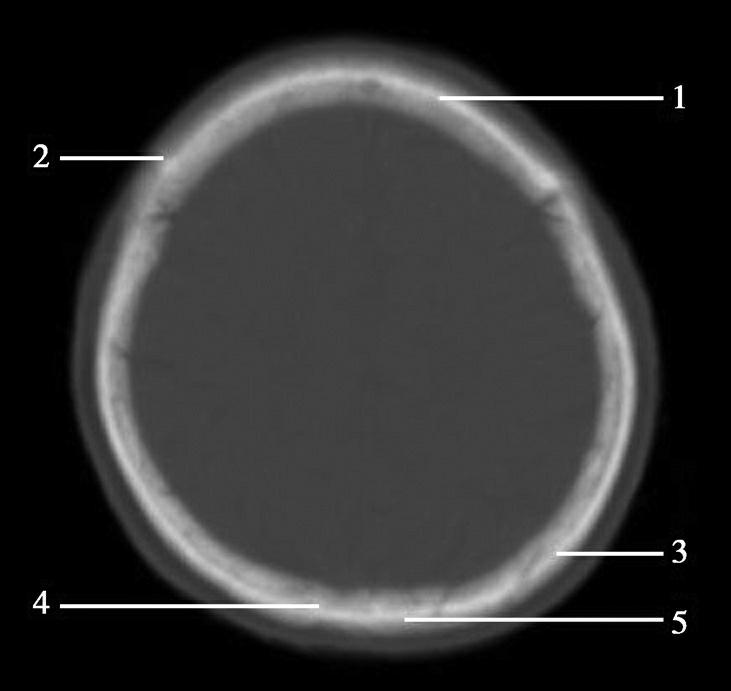

重要结构:卵圆孔、棘孔、破裂孔、斜坡、颞骨岩部、颈静脉孔(图1-2-1、图1-2-2)。

图1-2-1 颅底层面

A.横断面;B.横断面标注

1.晶状体;2.筛窦;3.颞肌;4.中颅窝底;5.外耳道;6.延髓;7.乙状窦;8.小脑半球;9.眼球;10.眼眶;11.上颌窦;12.蝶窦;13.乳突;14.耳郭;15.小脑蚓部;16.枕内隆凸

图1-2-2 颅底层面(骨窗)

1.鼻骨;2.筛窦纸板;3.颧骨眶突;4.翼腭窝;5.蝶骨大翼;6.卵圆孔;7.破裂孔;8.颞骨颧突;9.棘孔;10.斜坡;11.颞骨岩部;12.乳突;13.颈静脉孔;14.枕乳突缝;15.枕骨;16.枕内隆凸

层面前部呈开口向前的“V”字形,正中为鼻中隔,向两侧依次为筛窦和眼眶,眼眶内前部为眼球,后部为眶脂体。翼腭窝位于眼眶后部,窝内含有脂肪并有上颌神经通过。层面中部为蝶骨体,蝶骨体中部可见含气蝶窦,蝶窦后方为枕骨基底部,两者呈前后关系,其上面构成斜坡。蝶窦两侧为蝶骨大翼,其后外侧缘处由前向后可见卵圆孔和棘孔,分别有下颌神经和脑膜中动脉通过。斜坡外侧、岩骨尖前方为破裂孔。蝶骨大翼与眶外侧壁的颧骨借颧弓相连,颧弓和蝶骨大翼之间有咬肌及颞肌。层面中部外侧为外耳道。颞骨岩部呈“八”字形,相互之间借破裂孔软骨、蝶岩软骨结合和岩枕软骨结合连接。岩部后外侧的乳突部内可见乳突小房,乳突部与枕骨相接。岩骨后部可见颈静脉孔,内有颈内静脉、舌咽神经、迷走神经和副神经通过。层面后部为颅后窝,其内可见延髓,延髓前方为延髓前池,内有椎动脉,后外侧为小脑半球下部,后方为第四脑室、小脑扁桃体及小脑蚓部。

破裂孔、卵圆孔、棘孔及斜坡等均为重要的解剖结构,临床常见疾病如鼻咽癌常侵犯上述结构(图1-2-3)。颈静脉孔区较常见的肿瘤为颈静脉球瘤,常伴有颈静脉孔及其邻近骨质的破坏(图1-2-4)。